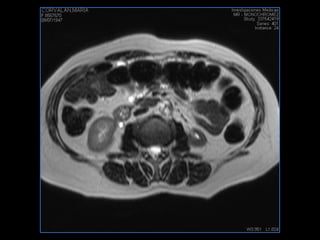

PROTOCOLO abdomen COR T2, AXIAL supresion grasa AX T1 +SAG T2  CON   GADOLINIO :  COR T1+AX T1(DIN) SAT: NO  FASE: RL THK: 6MM  COIL:  GAP: (FACTOR 1.4) 2MM FOV: 40 CM NEX:2 SINCRONIZACION RESPIRATORIA EN 3 O 4 CICLOS ALE

PROTOCOLO pancreas/ riñon AXIAL fat sat /AX in phase out phase AX T1 +SAG T2  COR T2, CON   GADOLINIO :  COR T1+AX T1(DIN) SAT: NO  FASE: RL THK: 4MM  COIL:  GAP: (FACTOR 1.4) 1MM FOV: 40 CM NEX:2 SINCRONIZACION RESPIRATORIA EN 3 O 4 CICLOS ALE